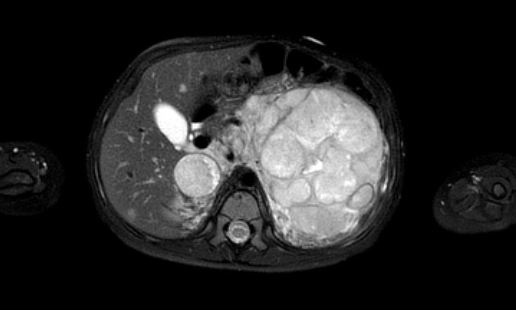

Hình ảnh

Hình ảnh MRI của một bé gái chín tháng tuổi có khối u ở bụng trái. MRI cho thấy khối u tuyến thượng thận trái, một phần đặc, một phần nang. Có nhiều di căn gan.

Khối u đã được sinh thiết. Có tình trạng chảy máu liên tục qua kim dẫn đường. Vào cuối thủ thuật, hai nút bọt gelatin đã được đặt vào (các dải tăng âm (mũi tên)).